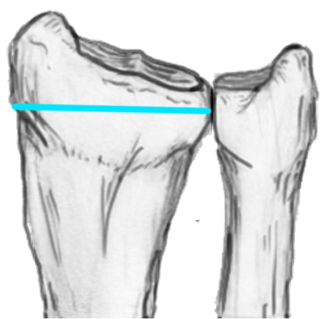

Unacceptable reduction

1. Distal radial Step > 2mm

3. Radial shortening > 5 mm

4. Radial inclination < 15o

5. Sagittal tilt

- > 15o dorsal

- > 20o volar